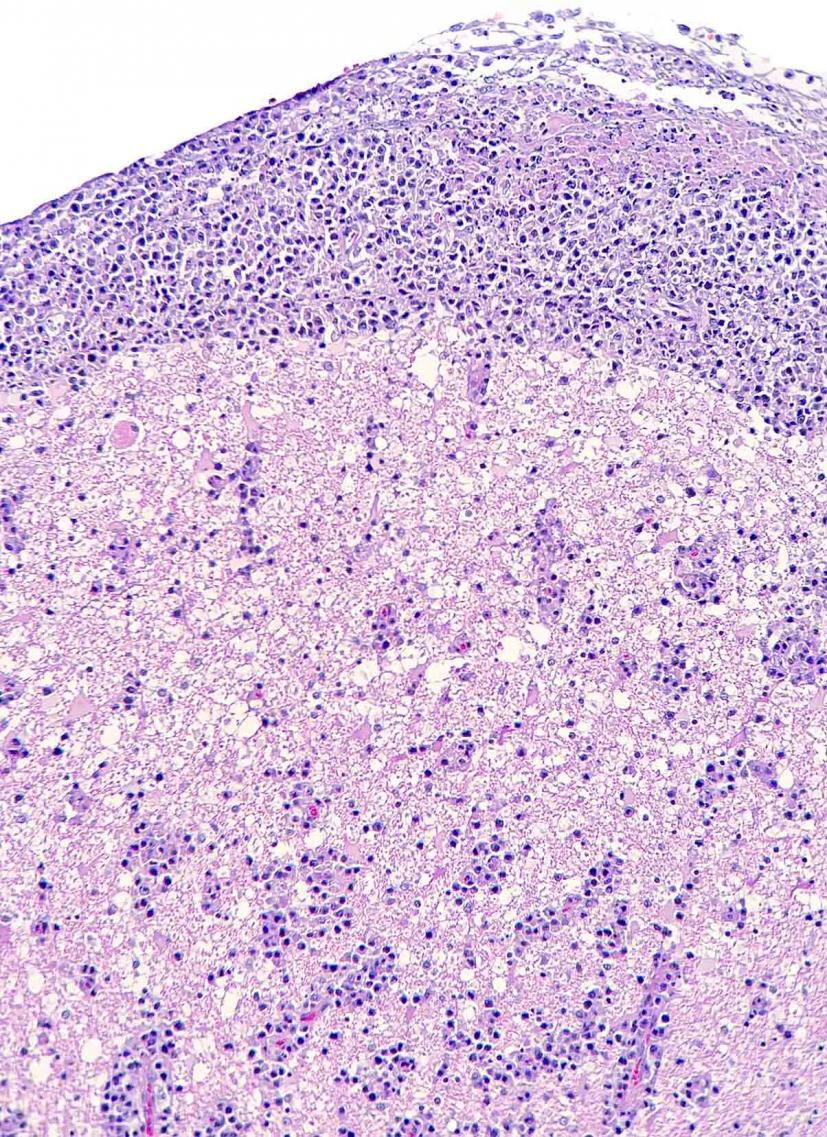

Este estudio, publicado en Transboundary and Emerging Diseases (2020; doi:10.1111/tbed.13713), ilustra el papel de la patología como herramienta de apoyo a los programas de conservación para especies en peligro de extinción. En este caso, la detección de dos herpesvirus presumiblemente nuevos en visones europeos se realizó a raíz del diagnóstico de un caso de linfoma principalmente neural/perineural con cuerpos de inclusión característicos de herpesvirus intralesionales en un visón europeo procedente del programa de cría en cautividad de esta especie amenazada. Estos virus podrían tener una influencia en el desarrollo de ésta y otras enfermedades que afectan a esta especie en cautividad y, por lo tanto, afectar a sus poblaciones.